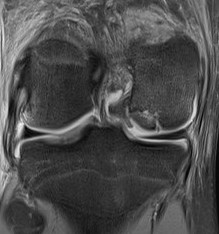

MFC OCD on presentation T2 image 6 months later

Stable lesion with no cysts Stable lesion with cysts